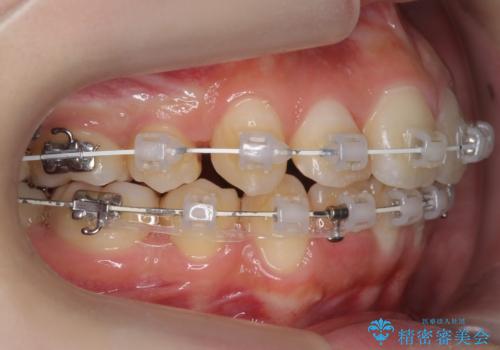

- ワイヤー矯正

- 3年1ヶ月

- 10-30回

抜歯してワイヤー矯正を行いました。